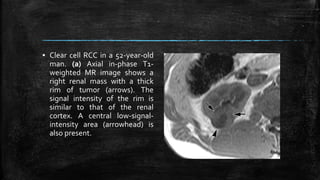

▪ Clear cell RCC in a 52-year-old

man. (a) Axial in-phase T1-

weighted MR image shows a

right renal mass with a thick

rim of tumor (arrows). The

signal intensity of the rim is

similar to that of the renal

cortex. A central low-signal-

intensity area (arrowhead) is

also present.

▪ Clear cellRCC in a 52-year-old man. (a) Axial in-phase T1- weighted MR image shows a right renal mass with a thick rim of tumor (arrows). The signal intensity of the rim is similar to that of the renal cortex. A central low-signal- intensity area (arrowhead) is also present.

▪ (b) Onan axial opposed-phase T1-weighted MR image, the mass appears homogeneous and is hypointense relative to the renal cortex.